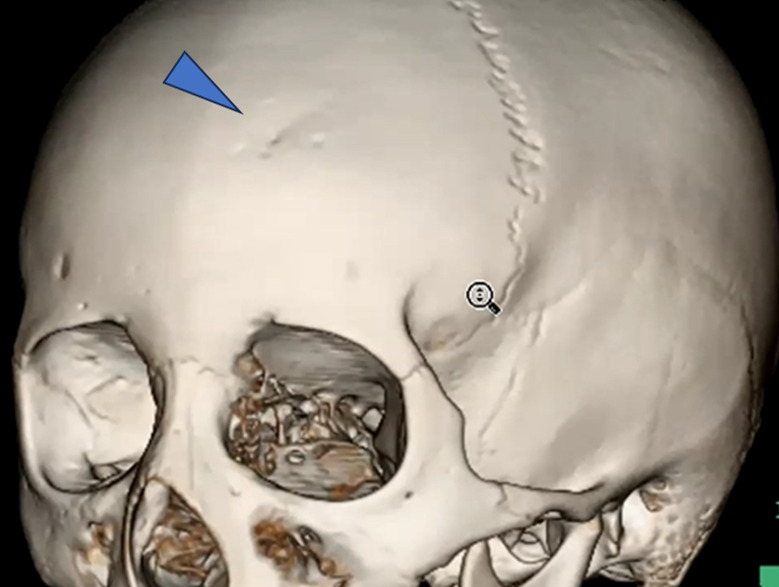

この時に最初のCT画像を振り返ると、実は”3D画像”がありました 。

画像がこちらです。

受傷部側の画像ですが、なにか気づきましたか?

受傷部の骨が一部陥没していることがわかります。

これを踏まえて、もう一度、骨条件の画像を確認しました。

一見すると異常が分かりにくい画像でも、3D画像を確認することで骨折の存在が明確になりました。

小児は骨が柔らかいため、外板のみが折れて陥没し、完全骨折に至らず所見が目立ちにくいことがあります。出血も初期は少量で、時間経過とともに明瞭化しました。本症例は外傷性陥没骨折、外傷性くも膜下出血・硬膜下血腫、脳挫傷と診断されました。